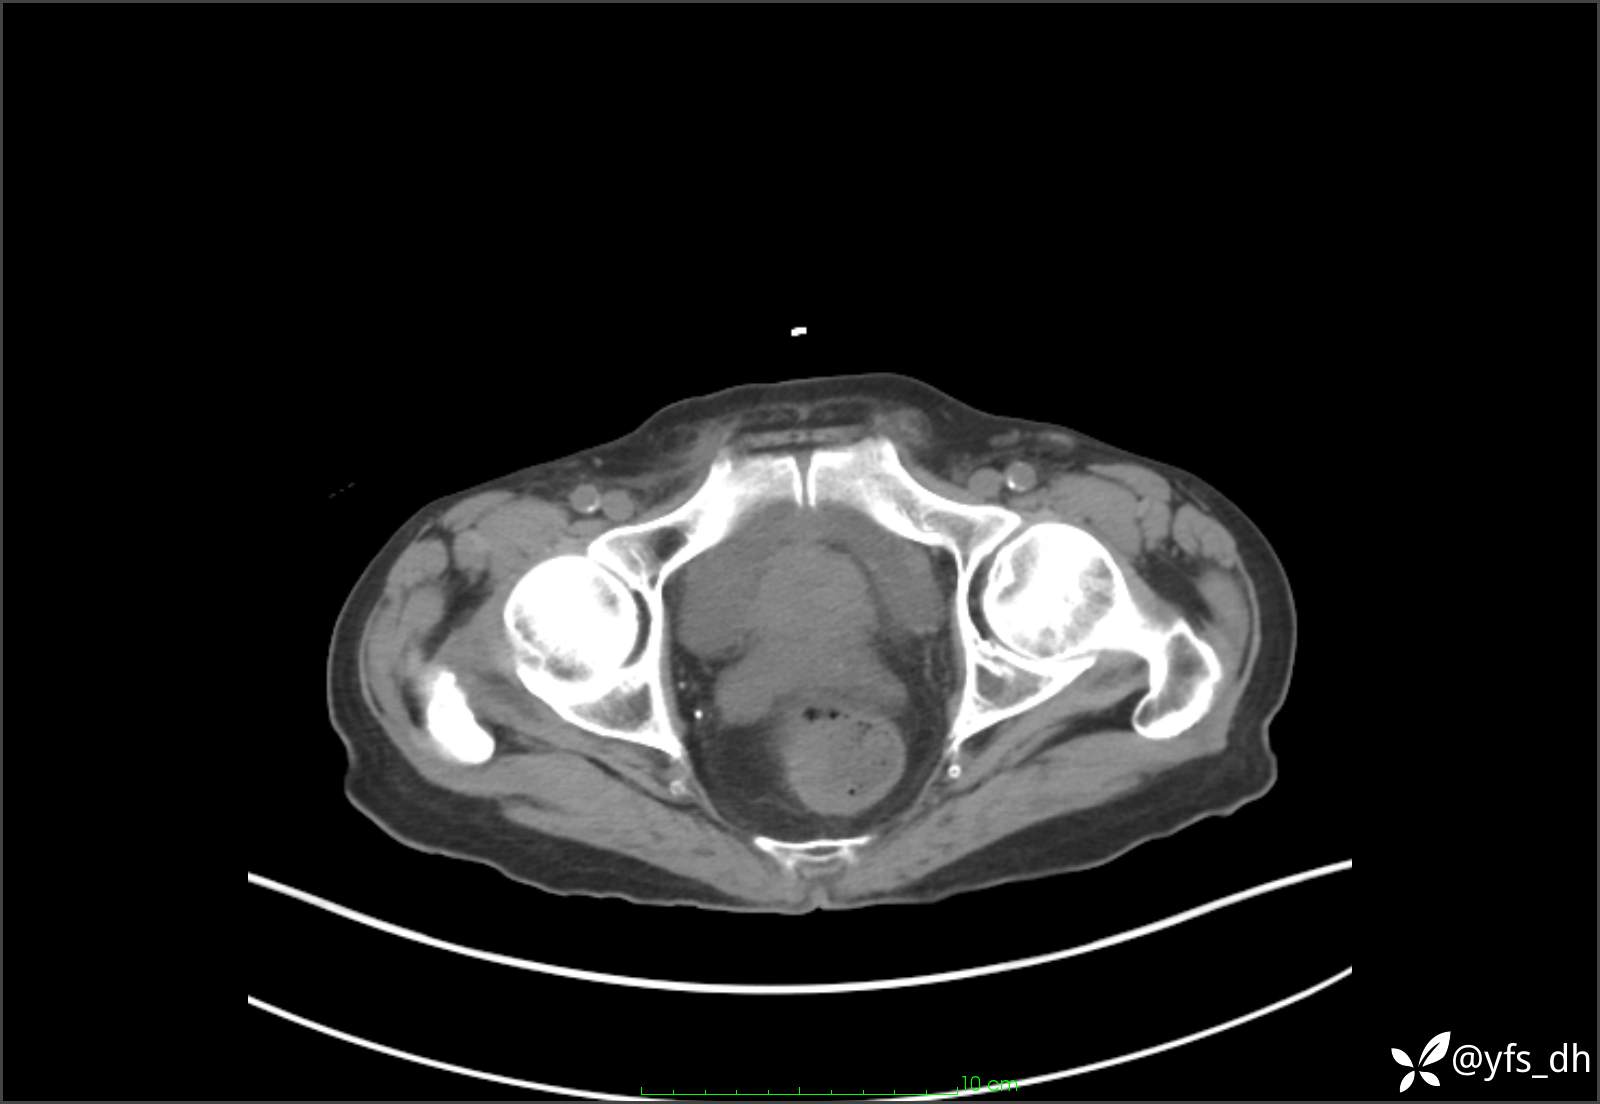

1.简要病史:患者4天前突发上腹部疼痛不适,但可以忍受。3小时前饭后突然加重,不能忍受后就诊。

2.简要手术记录:术中见腹盆腔大量肠液及粪便,乙状结肠中下段见一约3cm的破口。